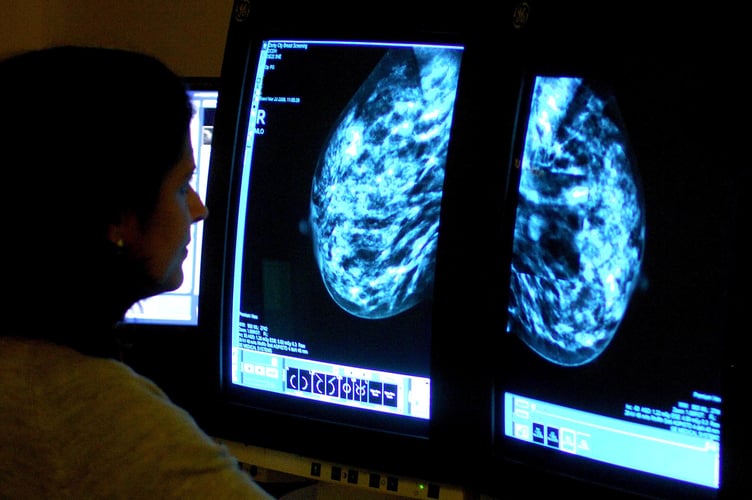

Any female aged between 50 and 71 and registered with a GP in England is offered an NHS breast screening every three years.

NHS England aims for seven in 10 women invited to undergo a screening.

In the year to March alone, 70% of the 2.5 million women invited underwent a screening. It was the first time the target has been met since 2018-19.

The figures show 16,677 women aged 45 and over had cancers detected through screening in the year to March, which corresponds to 8.5 cases per 1,000 women screened.

It was down from 18,942 cancers detected and a rate of 8.7 per 1,000 women screened the year before.